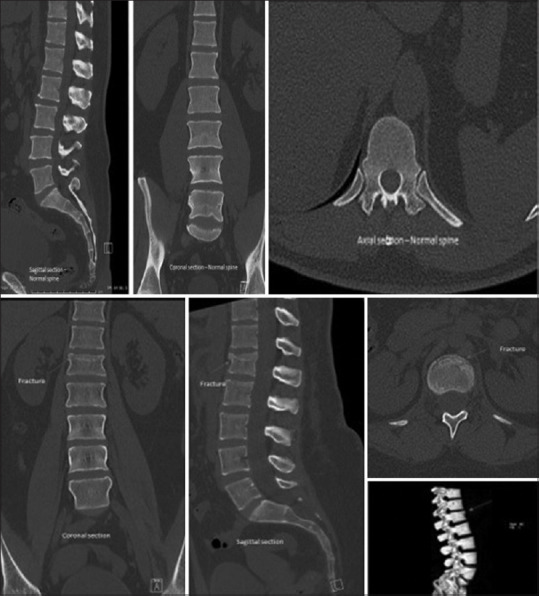

Introduction: The primary objective of this study was to assess the effectiveness of the clinical decision tool (CDT) in trauma patients, providing a comparable ability to rule out thoracolumbar (TL) fractures as traditional imaging methods. The goal is to facilitate early clearance of the TL spine without an immediate requirement for radiological tests, thereby minimizing unnecessary utilization of TL-spine imaging.

Methods: A prospective, observational study was conducted on trauma patients with suspected TL injury. To achieve early TL clearance, the CDT assessed criteria such as absence of pain, tenderness, and pain-free axial movement and flexion. The study enrolled alert trauma patients with thoracic and/or lumbar spine injuries, defined by the Glasgow Coma Scale of 15. The study excluded patients not aligning with CDT criteria, such as those who received intravenous opioid analgesia within 4 h and those unable to stand due to suspected pelvic or lower limb injuries.